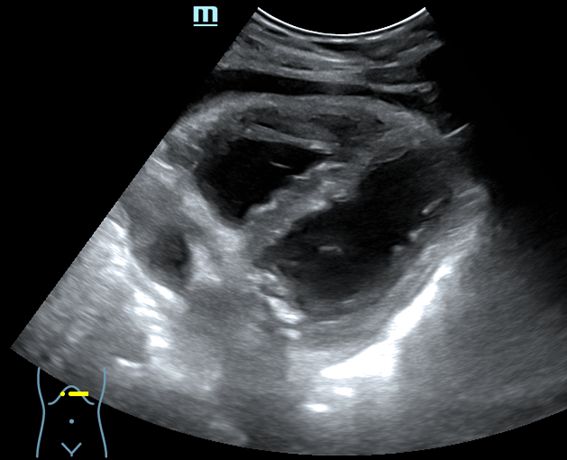

- Ecografía abdominal: ventana subxifoidea: buena contractilidad miocárdica, cámaras de tamaño normal, derrame pericárdico. Corte epigastrio: cava de tamaño y colapsabilidad normal.

Diagnóstico diferencial: la ecografía pulmonar descarta: neumotórax, derrame pleural y consolidación pulmonar. La ecografía abdominal descarta: tromboembolismo pulmonar, insuficiencia cardíaca y taponamiento cardíaco.

Juicio clínico: Pericarditis aguda (dolor centrotorácico + ascenso ST en casi todas las derivaciones + derrame pericárdico), pero surgió un problema: el EKG informaba que era un infarto inferior agudo.